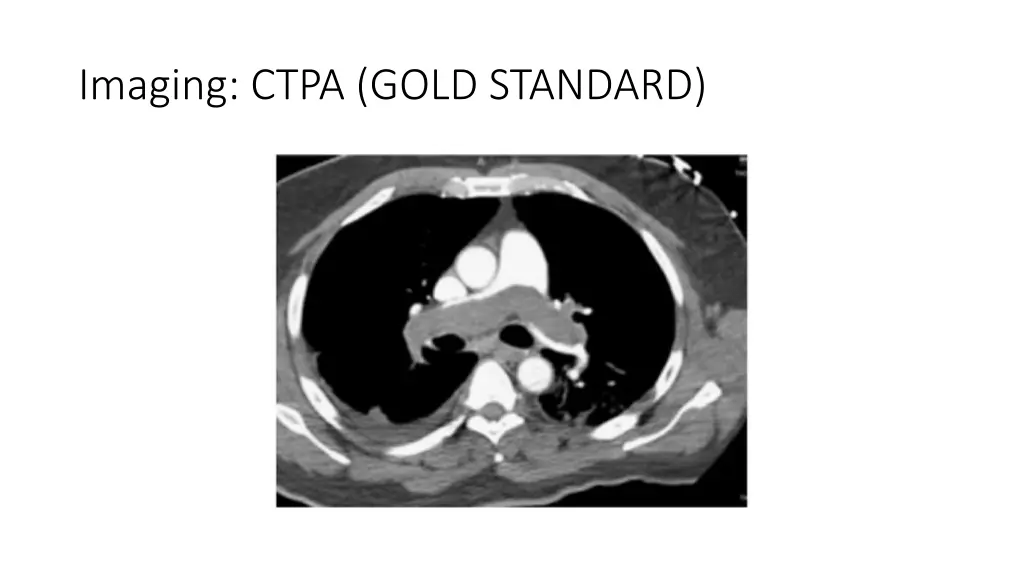

You are allowed to download the files provided on this website for personal or commercial use, subject to the condition that they are used lawfully. All files are the property of their respective owners.